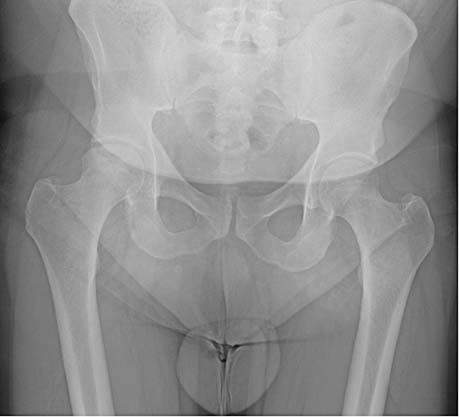

De orthopedisch chirurg vond bij het onderzoek van de knie geen bijzonderheden. Bij onderzoek van de rechterheup viel op dat met name de endorotatie beperkt en pijnlijk was. Röntgenfoto’s van de rechterheup toonden aanwijzingen voor een avasculaire femurkopnecrose met secundaire coxartrose [figuur 1]; een MRI bevestigde deze diagnose [figuur 2].